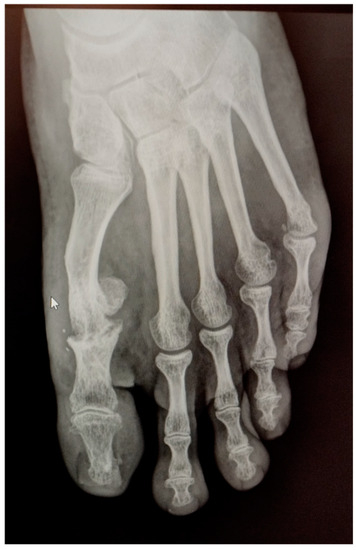

In May 2021, he underwent an operation to correct the hallux valgus deformity using chevron capital osteotomy and a proximal Akin procedure (Figure 1). The patient reported that a year later he had to be operated on again due to pain at the level of the first MPJ to remove the osteosynthesis material. The second surgery was performed outpatiently with epidural anaesthesia through a medial incision at the MPJ level (Figure 2).

Figure 1. Postoperative radiological aspect of foot after the first procedure.